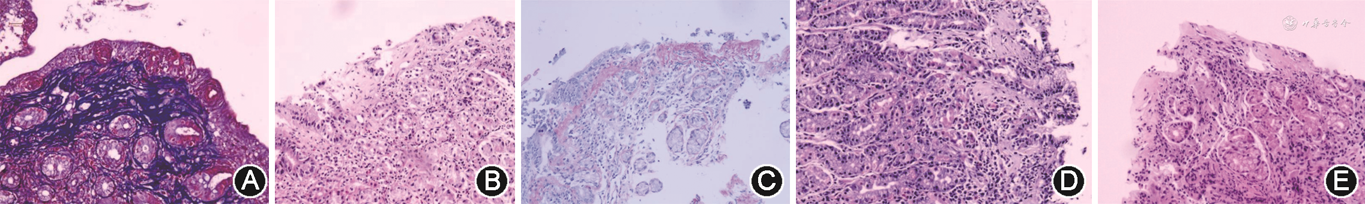

入院查体:神志清,面色苍白,心、肺、腹部及神经系统查体无异常。辅助检查:血常规示血红蛋白降低(65 g/L)。铁代谢示血清铁降低(3.9 μmol/L),铁蛋白降低(5.0 μg/L),不饱和铁结合力升高(79.9 μmol/L),总铁结合力升高(83.8 μmol/L),转铁蛋白饱和度降低(5%)。血清维生素B12、叶酸、超敏C反应蛋白、抗核抗体及抗中性粒细胞胞质抗体均未见异常。骨髓穿刺示缺铁性贫血。胃镜示胃体黏膜颗粒状隆起,胃底、胃窦黏膜粗糙,十二指肠球部及降部绒毛扁平,黏膜粗糙。快速尿素酶试验(rapid urease test,RUT)阴性。结肠镜无殊。组织病理学示胃体及胃底黏膜中度慢性炎,表面上皮损伤、脱落,上皮下局灶、斑片状嗜酸性胶原沉积,最厚处134 μm及167 μm。十二指肠球部及降部绒毛萎缩,黏膜下见斑片状胶原沉积,最厚处161 μm及56 μm。球部嗜酸粒细胞计数约65个/高倍镜视野。胃窦、回肠末端及结直肠黏膜无异常。Masson 三色及天狼猩红染色见不规则胶原沉积(图1A);美兰、刚果红染色阴性。诊断为胶原性胃炎(collagenous gastritis,CG)并累及十二指肠。

入院查体:神志清,皮肤口唇苍白。腹软,剑突下有压痛,无反跳痛。辅助检查:血常规示血红蛋白降低(84 g/L),网织红细胞计数升高(0.076)。骨髓穿刺示缺铁性贫血。铁代谢示血清铁降低(2.8 μmol/L),铁蛋白降低(3.6 μg/L),不饱和铁结合力升高(65.6 μmol/L),转铁蛋白饱和度降低(4%)。粪潜血阳性。叶酸、维生素B12、超敏C反应蛋白、葡萄糖6-磷酸脱氢酶活性、胃泌素、抗中性粒细胞胞质抗体、抗核抗体、免疫球蛋白、补体、抗壁细胞及抗细胞因子抗体检测均无殊。胃镜示胃底、胃体黏膜粗糙伴萎缩、水肿和红斑,部分疣状隆起,胃窦黏膜粗糙,十二指肠黏膜水肿。RUT阴性。结肠镜无殊。组织病理学示胃体黏膜中度慢性炎,上皮损伤脱落,上皮下见斑片状胶原沉积,最厚处154 μm(图1B)。胃体嗜酸粒细胞计数约58个/高倍镜视野。胃窦、十二指肠及结直肠黏膜无异常。Masson 三色及天狼猩红染色见不规则胶原沉积(图1C);美兰、刚果红染色阴性。诊断为CG。

入院查体:神志清,面色苍白,下腹轻压痛,无反跳痛。辅助检查:铁代谢示血清铁降低(3.3 μmol/L),铁蛋白降低(3.0 μg/L),不饱和铁结合力升高(80.3 μmol/L),总铁结合力升高(83.6 μmol/L),转铁蛋白饱和度降低(4%)。钙卫蛋白升高(361 μg/g)。超敏C反应蛋白、叶酸、维生素B12、抗核抗体、抗中性粒细胞胞质抗体、免疫球蛋白及补体均无殊。胃镜示胃体黏膜弥漫性结节样隆起(图2),胃窦及十二指肠黏膜无殊。RUT阴性。胶囊内镜及结肠镜无殊。组织病理学示胃体黏膜呈中度慢性炎,部分上皮脱落,隐窝上皮内淋巴细胞增多(>25个/100个表面上皮),淋巴细胞无异型。上皮下见斑片状胶原沉积(图1D),最厚处68 μm。胃体嗜酸粒细胞计数约18个/高倍镜视野。胃窦、小肠及结直肠黏膜无异常。Masson三色及天狼猩红染色见不规则胶原沉积;美兰、刚果红染色阴性。诊断为CG。

入院查体:神志清,睑结膜、口唇面色苍白,腹部查体无异常。辅助检查:免疫球蛋白及补体测定示IgG4升高(2.46 g/L),余正常。超敏C反应蛋白、红细胞沉降率、抗核抗体、葡萄糖6-磷酸脱氢酶活性均正常。胃镜示胃底、胃体黏膜弥漫性粗糙,颗粒样隆起。胃窦黏膜充血水肿。十二指肠球部黏膜粗糙、糜烂,降部黏膜光滑。RUT阴性。组织病理学示胃窦及胃底黏膜中度慢性炎,上皮部分脱落,上皮下见斑片状胶原沉积,最厚处126 μm及124 μm。胃窦嗜酸粒细胞计数约45个/高倍镜视野。胃体黏膜未取活检组织。十二指肠球部黏膜绒毛萎缩,上皮下见斑片状胶原沉积(图1E),最厚处72 μm。降部黏膜无殊。Masson 三色及天狼猩红染色见不规则胶原沉积;美兰、刚果红染色阴性。诊断为CG并累及十二指肠。